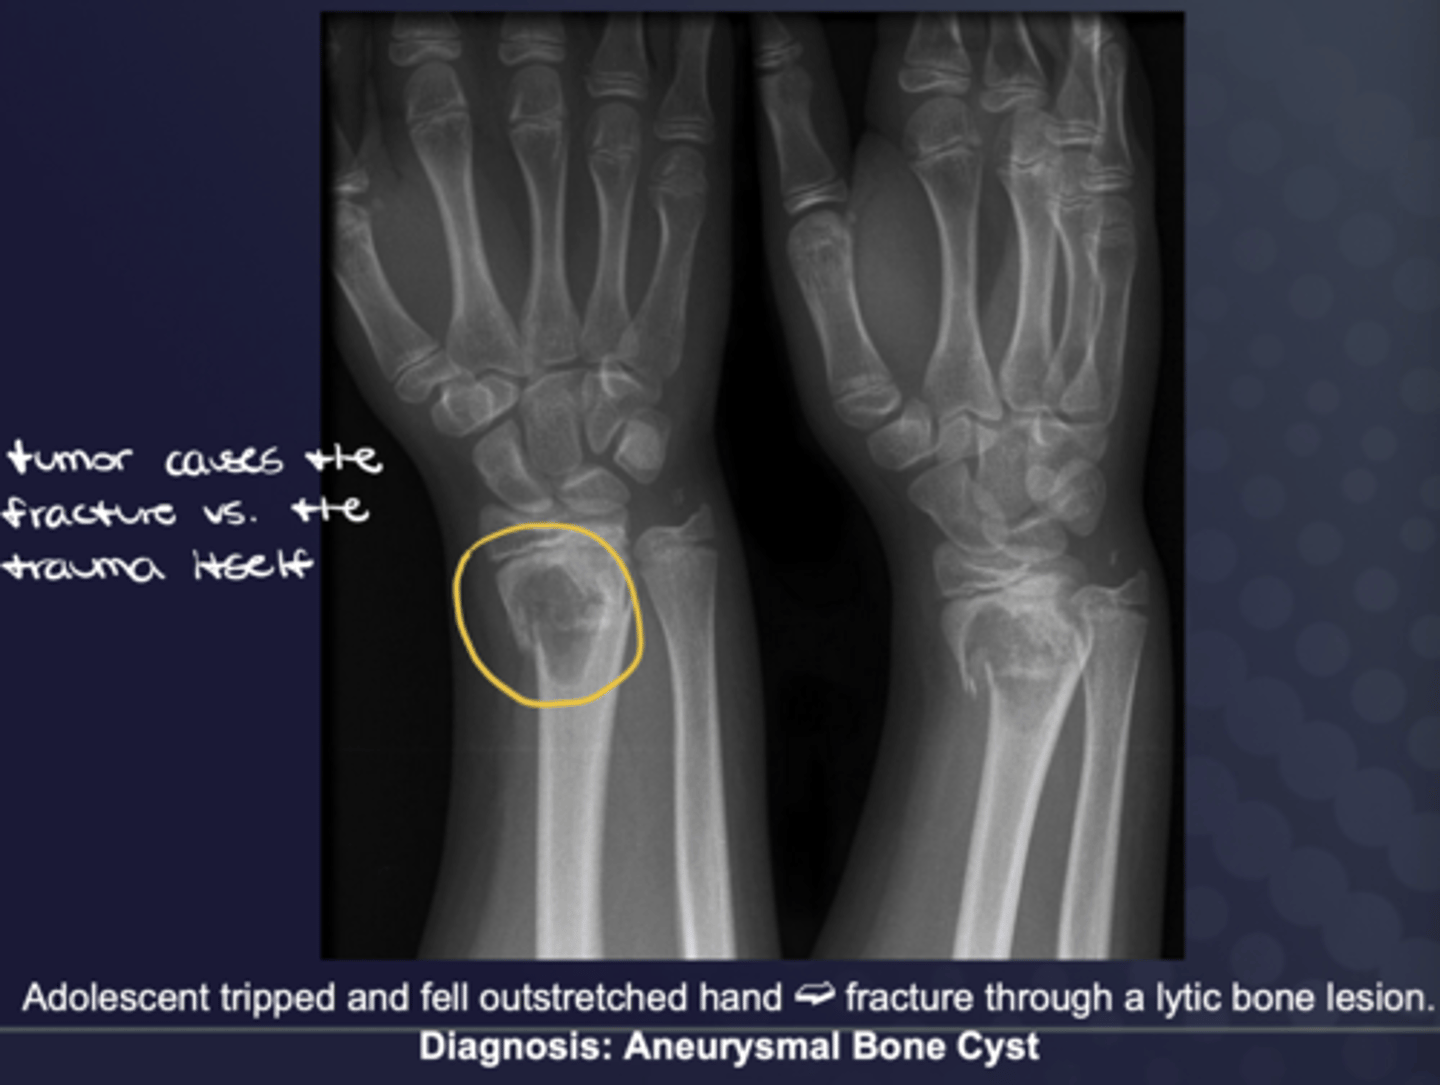

Stress fractures and pathological fractures (i.e., if bone breaks w/o trauma)

What are some ways pathology weakens bone?

Tumor, osteoporosis, infection, Paget's disease

If the bone is normal and the bone breaks WITHOUT trauma, what is this known as?

Stress fracture